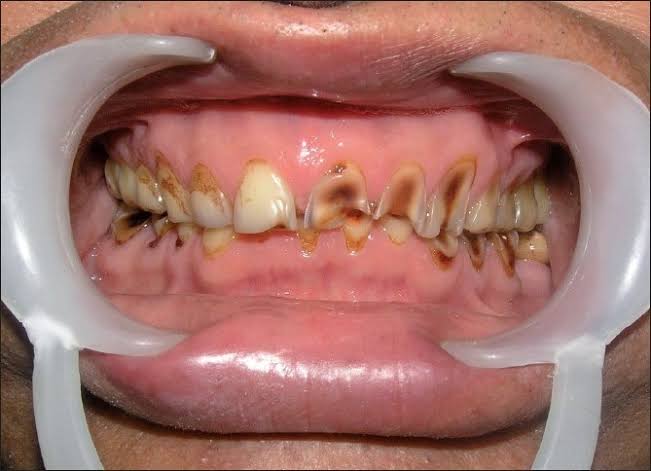

Patient wanted to get a new set of new teeth as old teeth were severely attrited and he was not able to chew. Medical history was taken and patient was fit for all the dental procedure. A detailed radiographic examination was conducted with the help of opg Treatment planning. A detailed case history along with radiological investigation and recording of of Bite of patient it was done in first visit. An appliance to relieve occlusion was given for 21 days Root canal treatment it was perform for all the teeth in subsequent visits. Occlusion was recorded using a specialised semi adjustable articulator. A temporary prosthesis was given to be used for or 15 days. A permanent Restoration was fabricated using pfm Crowns. A patience on patient end is a much needed thing as it involves time duration of of 1 to 2 months. Patient has to be absolutely serious about the treatment protocols which we are following as it involves use of appliances on patients end. Patient has to leave habit of eating Supari and tobacco as it was the cause in in severe reservation and attrition of teeth the artificial prosthesis is a finely crafted instrument that needs to be used with precision. so patients willingness and a positive mindset is Paramount in treating such cases.

Exciting News! Discover the Steps of Full Mouth Rehabilitation for a Dazzling Smile! Are parafunctional habits like kharra and ghutka taking a toll on your dentition? Say goodbye to improper chewing, loss of facial aesthetics, and digestive troubles with our expert team at Chintamani Dental Clinic!